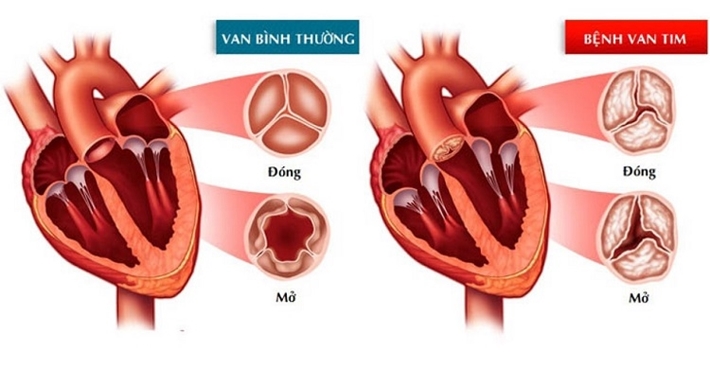

Phẫu thuật van tim là một thủ thuật điều trị bệnh van tim. Bệnh van tim liên quan đến ít nhất một trong 4 van tim không hoạt động bình thường. Các van tim giữ cho máu chảy theo hướng chính xác qua tim.

Bốn van tim là van hai lá, van ba lá, van động mạch phổi và van động mạch chủ. Mỗi van có các nắp – được gọi là các lá chét cho van hai lá và van ba lá và các nắp cho van động mạch chủ và van động mạch phổi. Các cánh này phải mở và đóng một lần trong mỗi nhịp tim. Các van không mở hoặc đóng đúng cách sẽ làm gián đoạn lưu lượng máu từ tim đến cơ thể.